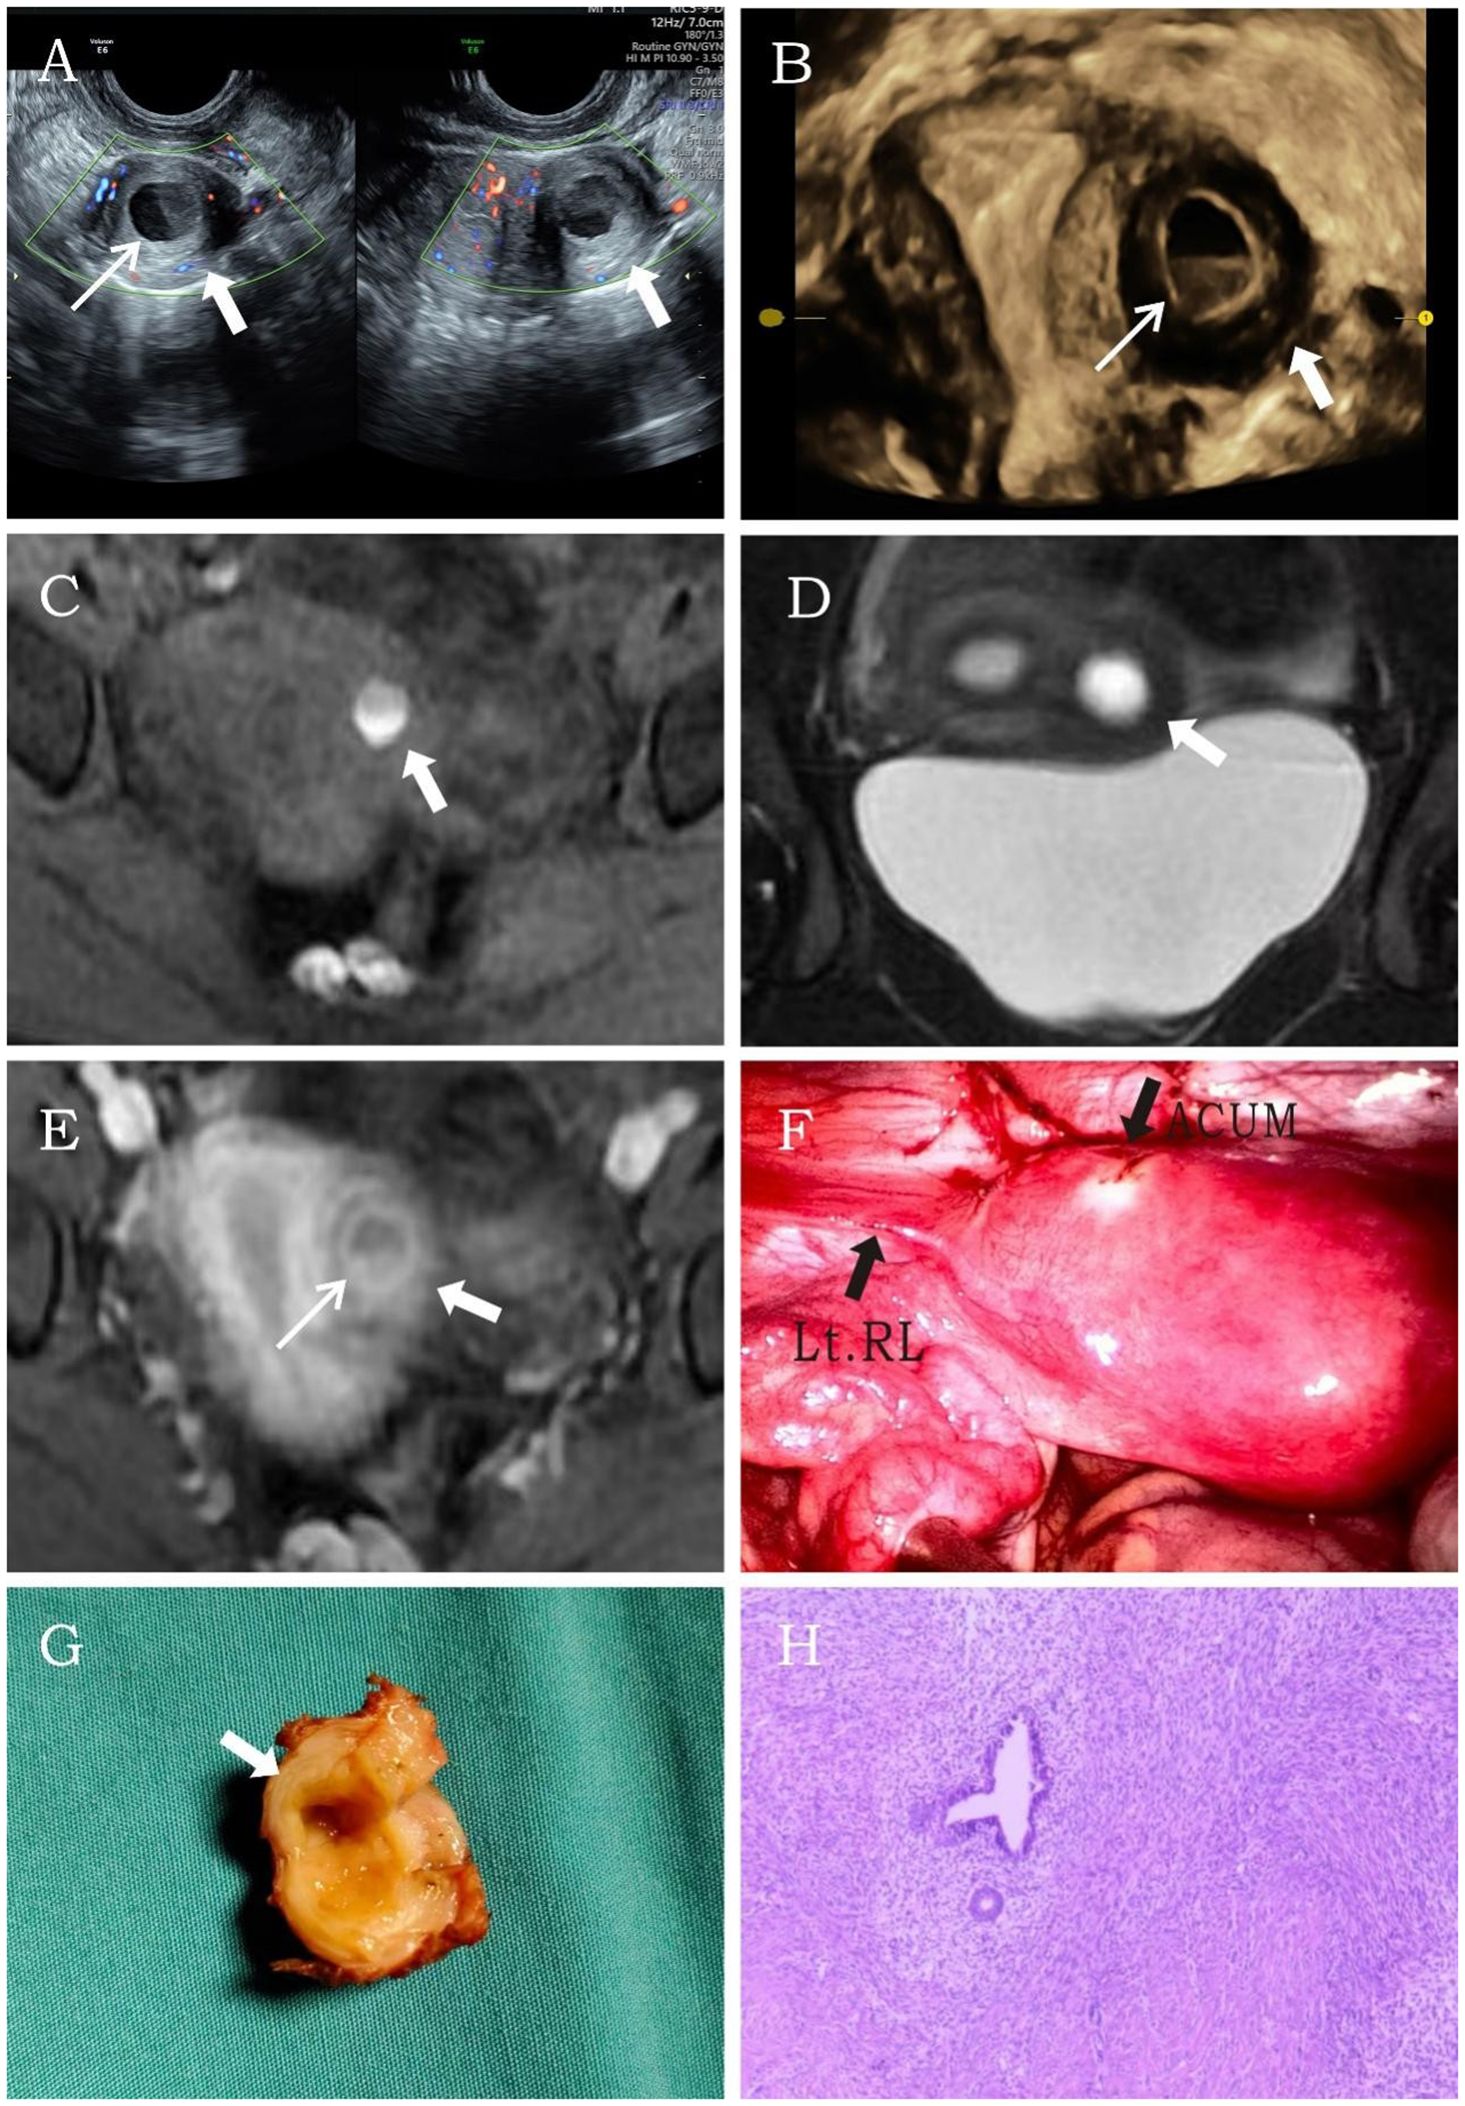

A 14.5-year-old female patient, unmarried and nulliparous, was admitted with dysmenorrhea for 1 year. Menarche occurred at 13 years, with dysmenorrhea developing 6 months later, progressively worsening throughout the menstrual cycle, and even starting 2 to 3 days before menstruation. She had been diagnosed with cystic adenomyoma by ultrasound examination at a local hospital 1 year earlier. Physical examination identified a mass in the left uterine wall with moderate consistency, limited mobility, and no tenderness. Laboratory tests showed no abnormalities. Transvaginal sonography conducted at our institution identified a well-circumscribed, thick-walled cystic mass (24 × 20 × 22 mm) in the left uterine myometrium, featuring a ground-glass echogenic cavity (14 × 11 × 12 mm) with characteristic endometrial lining (1.0 mm) and a surrounding hypoechoic muscular rim (4.6 mm). The uterine cavity appeared normal, and no abnormalities were detected in either adnexal region. Color Doppler flow imaging (CDFI) revealed a semicircular blood flow signal surrounding the cystic mass (Figures 1A, B). The ultrasound diagnosis was ACUM. MRI showed a round abnormal signal focus in the left uterine myometrium with heterogeneous internal signals: slightly hyperintense (upper layer) and hyperintense (lower layer) on T1WI (Figure 1C) and hyperintense on T2WI (Figure 1D). Contrast-enhanced imaging showed gradual mild-to-moderate enhancement of the surrounding cystic wall (Figure 1E). The MRI diagnosis was cystic adenomyosis or rudimentary horn uterus. The patient was diagnosed with ACUM by laparoscopic surgery (Figures 1F–H) and underwent ACUM resection. During the 12-month postoperative follow-up, the patient remained asymptomatic with no recurrence.

Figure 1. Representative image of clinical data for the first case. (A, B) Transvaginal and four-dimensional ultrasound images reveal a thick-walled cystic mass (thick white arrow) within the left lateral wall of the uterine myometrium. A thin endometrial-like ring (thin white arrow) is seen along the inner wall of the cavity, while the remaining uterine structure appears normal. (C–E) MRI demonstrates an abnormal signal focus (thick white arrow) in the left lateral myometrium. The T1-weighted fat-suppressed sequence shows high signal intensity within the cavity resembling hematometra. Post-contrast imaging reveals a thin endometrial-like slightly hyperintense signal (thin white arrow) along the inner wall. The T2-weighted image displays a low signal surrounding the inner wall, similar to the myometrium. (F) Laparoscopy shows a protruding mass at the insertion site of the round ligament of the uterus. (G) After incision, the cystic cavity is surrounded by a regular, thick layer of muscular tissue (thick white arrow). (H) Histopathological image (H&E, ×10). The submitted smooth muscle tissue is partially lined by hyperplastic endometrium, with scattered endometrial glands and stroma within the muscular wall.